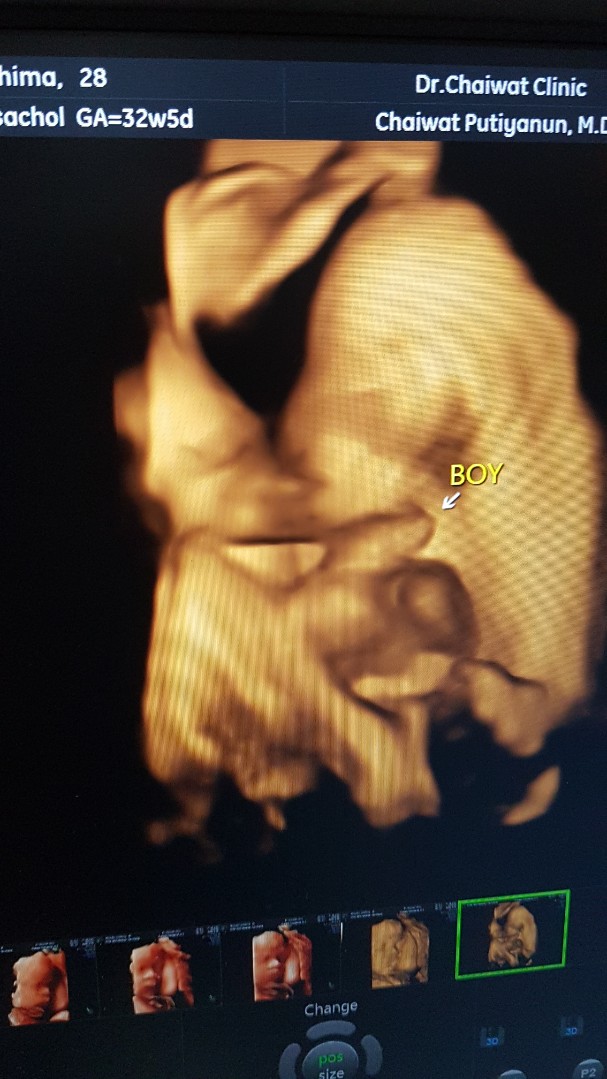

BOY